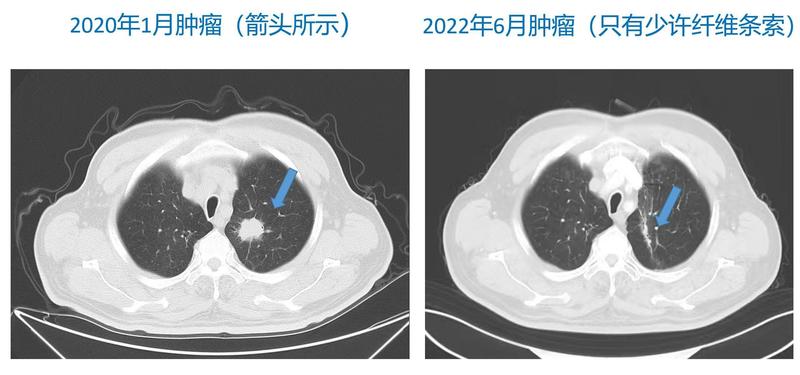

本周一名老患者來院復(fù)查,患者孩子非常孝順,知道我會在報告出之前給患者看看片子,能提前大半天知道結(jié)果。因為各種原因,患者已有半年未來復(fù)查,打開CT片的過程中,家屬滿臉都是忐忑。最后確認(rèn)沒有腫瘤,臉上的開心溢滿我整個辦公室,讓我回想起老人的治療過程。2020年1月無明顯誘因出現(xiàn)咳嗽、咳少量白色粘痰,四肢骨關(guān)節(jié)腫脹及疼痛,右側(cè)坐骨疼痛不適,無痰中帶血,無胸悶、憋氣,無寒戰(zhàn)、發(fā)熱。CT檢查:“1.考慮左肺上葉癌,左肺門、縱隔淋巴結(jié)腫大,考慮轉(zhuǎn)移;2.右肺小結(jié)節(jié)灶,建議觀察。MRI檢查:“結(jié)合臨床,考慮骶骨右側(cè)側(cè)、右側(cè)側(cè)髖臼轉(zhuǎn)移;病理檢查:“(肺穿刺活檢)腺癌”。基因檢測無敏感突變。IV期腺癌,不能靶向治療,家屬非常焦慮,覺得沒有治愈希望了。我跟他溝通,雖然有骨轉(zhuǎn)移,但屬于寡轉(zhuǎn)移(不超過3-5個轉(zhuǎn)移灶),仍有治愈的希望,他那時候?qū)⑿艑⒁?,跟我確認(rèn)了很多遍是不是真的還能治好。結(jié)合當(dāng)時的治療指南,制定了全身治療為主,局部放療的模式。因為骨轉(zhuǎn)移有癥狀,給予骨轉(zhuǎn)移部位放療,同時給予雙磷酸鹽及補鈣。全身治療,無敏感突變,給予“培美曲塞+順鉑”化療,同時給予“PD-1單抗“”免疫治療。很快患者骨轉(zhuǎn)移部位疼痛癥狀明顯減輕,第一次復(fù)查CT病變就顯著好轉(zhuǎn)。2020年9月肺部病灶不再縮小,和家屬商討,是胸部放療介入的時機,于是給予根治量的放療。2021年12月見肺內(nèi)有炎癥,考慮患者無明顯腫瘤負(fù)荷,暫停免疫,患者無發(fā)熱胸悶不適。2021年1月炎癥好轉(zhuǎn),繼續(xù)PD-1單抗。后因各種原因于2021年8月停用免疫治療,患者進入定期復(fù)查階段。2022年6月,患者自患病至今已達2年4月余,復(fù)查沒有腫瘤,且心情好、生活如同正常人。我真心的和家屬一樣高興,能和患者及家屬同頻共振的就是我們醫(yī)生了,希望每個患者都能治愈,復(fù)查都沒有腫瘤進展。分享這個患者故事,是想和大家溝通3個方面:1.腫瘤治療邁入多元化治療時代,新的治療方法極大的延長了生存,并不是IV期患者發(fā)生遠(yuǎn)處轉(zhuǎn)移,就沒有治療價值。2.很多研究證實放療和免疫有協(xié)同作用,能給予更好的治療效果。3.免疫治療有記憶作用,部分患者停藥后,有持續(xù)的免疫應(yīng)答。